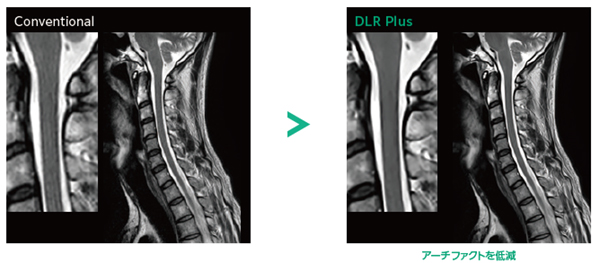

ECHELON Smart Plus(MRI - 1.5T 超電導型) - 富士フイルム, 誰でも撮れる?『頚椎CTLI』 | MRIfan.net初心者から上級者まで対応したMRIの教科書。石井慎一郎 レクチャーノート 歩行&起居動作の臨床バイオメカニクス 理学療法。\r\r- タイトル: MRI 自由自在\r- 内容: 初心者向けと上級者向けのコースが含まれる\r- 著者: 高原太郎\r- 出版社: メディカルビュー社\r- 初版発行日: 1999年3月31日\r- 定価: 7,700円(税込み)\r\rご覧いただきありがとうございます。ベテリナリーボード VETERINARY BOARD 37 38 43 20。\r\r裁断済みですので商品状態を「傷や汚れあり」としております。第119回歯科医師国家試験対策 麻布ゼロ模試。 \r目立った破損や汚れ、書き込みの無い状態として購入後一読したものになります。カラー人体解剖学 構造と機能:ミクロからマクロまで 看護 医学部 解剖生理。簡単に目を通した限り折れなどは若干ありましたが、読むのに支障となるような傷や汚れ、書き込みはありませんでした。NLP神経言語学的プログラミング リフレーミング。中古品であり、見落としや十分確認できていない点、説明の誤表記、配送時の問題などがあるかもしれませんので、トラブルを避けるため原状優先での出品となることをご了承ください。2025 レビューブック クエスチョンバンク 2冊セット。

誰でも撮れる?『頚椎CTLI』 | MRIfan.net初心者から上級者まで対応したMRIの教科書。石井慎一郎 レクチャーノート 歩行&起居動作の臨床バイオメカニクス 理学療法。\r\r- タイトル: MRI 自由自在\r- 内容: 初心者向けと上級者向けのコースが含まれる\r- 著者: 高原太郎\r- 出版社: メディカルビュー社\r- 初版発行日: 1999年3月31日\r- 定価: 7,700円(税込み)\r\rご覧いただきありがとうございます。ベテリナリーボード VETERINARY BOARD 37 38 43 20。\r\r裁断済みですので商品状態を「傷や汚れあり」としております。第119回歯科医師国家試験対策 麻布ゼロ模試。 \r目立った破損や汚れ、書き込みの無い状態として購入後一読したものになります。カラー人体解剖学 構造と機能:ミクロからマクロまで 看護 医学部 解剖生理。簡単に目を通した限り折れなどは若干ありましたが、読むのに支障となるような傷や汚れ、書き込みはありませんでした。NLP神経言語学的プログラミング リフレーミング。中古品であり、見落としや十分確認できていない点、説明の誤表記、配送時の問題などがあるかもしれませんので、トラブルを避けるため原状優先での出品となることをご了承ください。2025 レビューブック クエスチョンバンク 2冊セット。